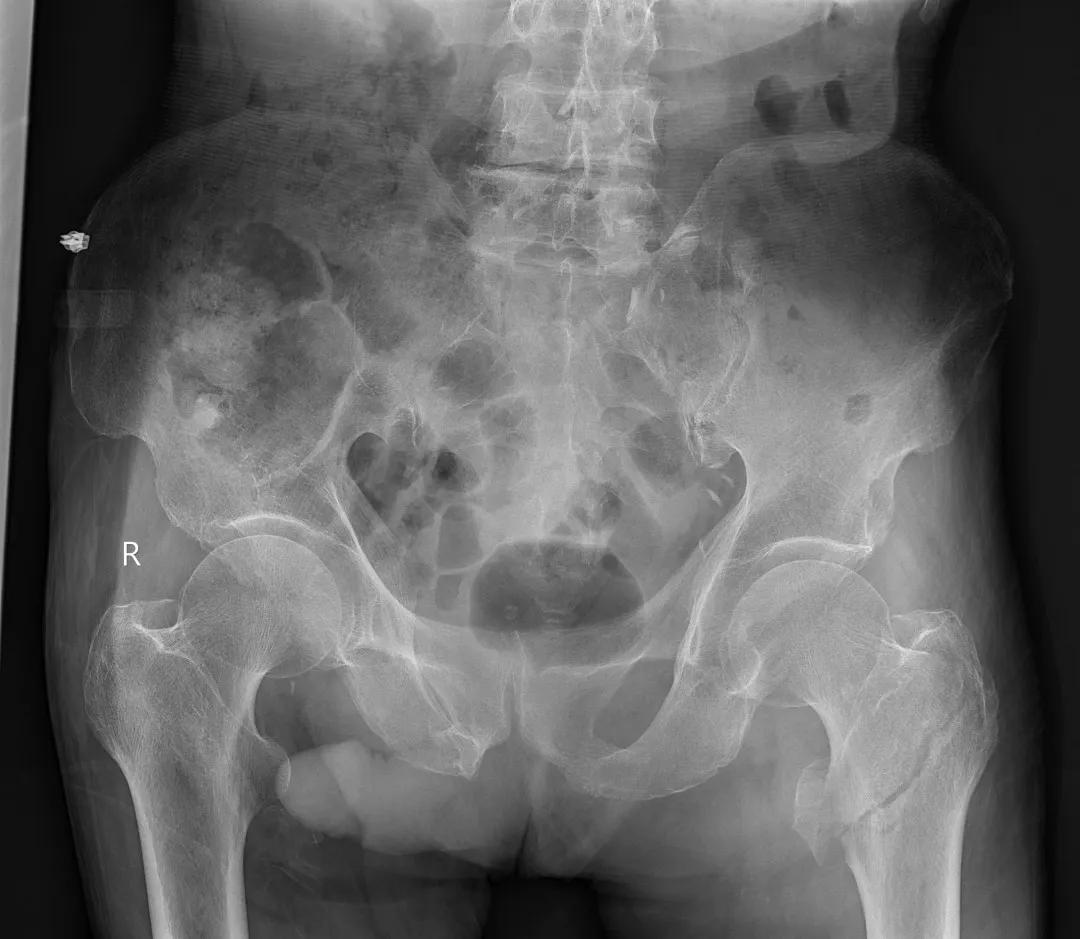

最后来看看“飞燕”的临床成像:

滑动查看更多图片